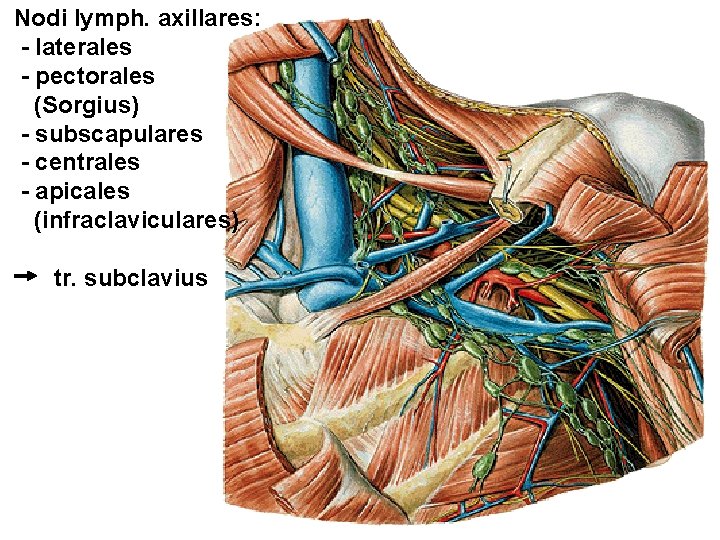

Nodi lymph. axillares: - laterales - pectorales (Sorgius) - subscapulares - centrales - apicales (infraclaviculares) tr. subclavius